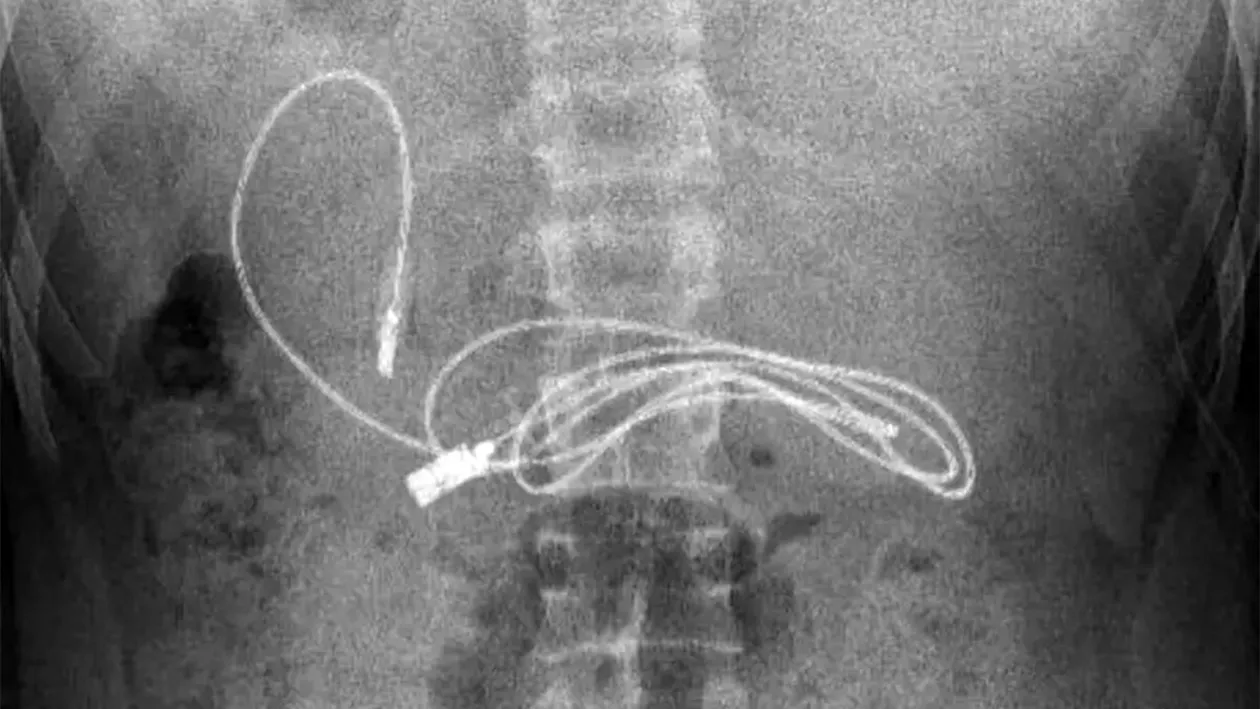

Când medicul gastroenterolog i-a văzut radiografia a stabilit clar că adolescentul a înghițit un cablu USB pentru telefon și căști. Pentru a reuși să-l extragă, i-a făcut o endoscopie și o mică incizie. Mai mult de atât, cablul era înconjurat de păr care, la fel, nu se știe cum a ajuns acolo. Tânărul nu a vrut să spună cum a reușit să își introducă gadgetul în stomac.

Cea mai grea parte în procesul de îndepărtare al gadgetului din stomac a fost că era atât de lung, încât o parte reușise să treacă în intestinul subțire, după cum a dezvăluit medicul.

„În mod evident, ne-a fost greu să scoatem cablul, deoarece un capăt al cablului a trecut în intestinul subțire”, a spus gastroenterologul pediatru Yasar Dogan.